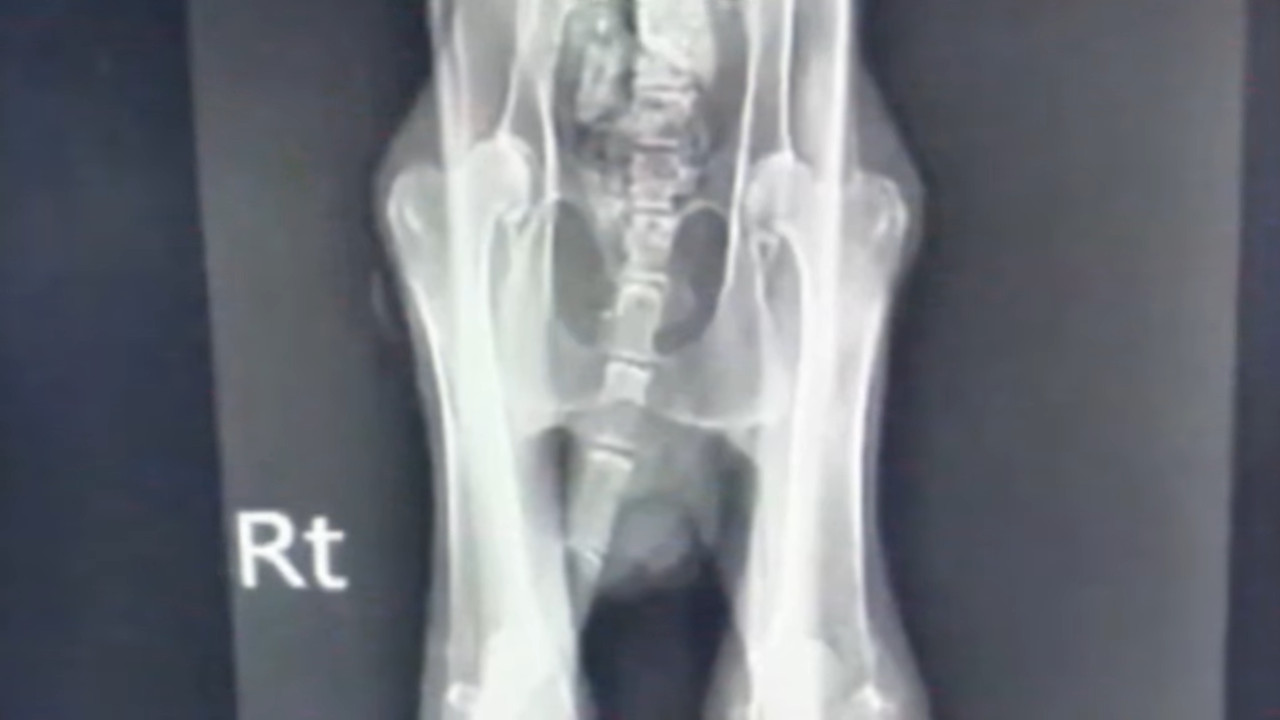

Veterinarians confirmed the broken tail and bones, and severe malnutrition. They quickly began treatment, preparing the cat for surgery.